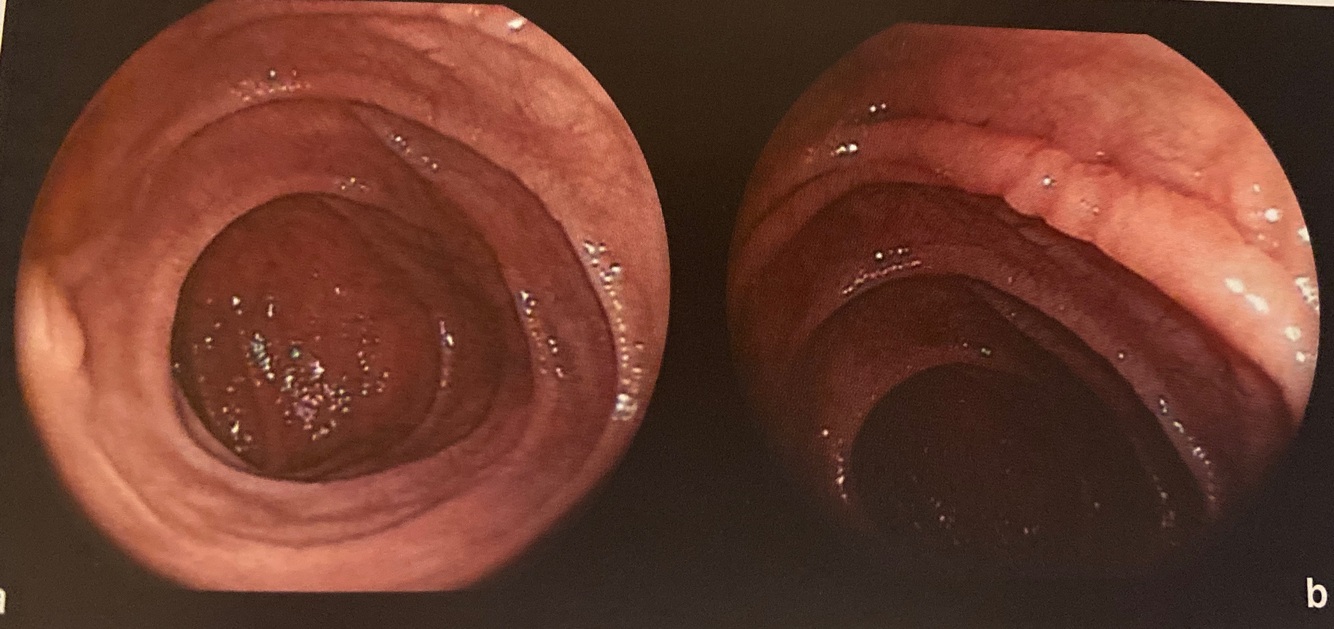

Q

Descrição duodenal

a e b Segunda porção duodenal com redução nítida do pregueamento mucoso e aspecto nodular das pregas (scalloping of folds)